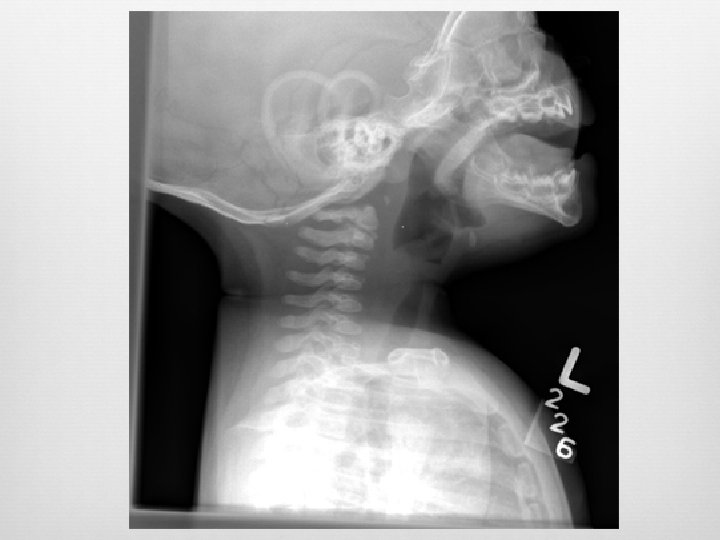

Retropharyngeal Infection Widened retropharyngeal space C 2 – 7 mm or C 6 – 14 mm (kids) C 6 – 22 mm (adults) Reversal of normal cervical lordosis Foreign body Air-fluid level Gas

False Pre-vertebral Swelling Oblique lateral Neck flexion Crying